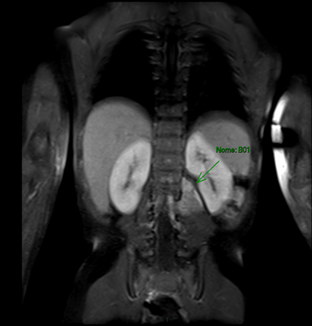

Paciente, sexo masculino, 11 meses, 10 kg, com diagnóstico de neuroblastoma e quadro clínico inicial de parestesia em membros inferiores, apresentando massa com invasão de canal medular em L1-L3, N-myc negativo, em tratamento pelo protocolo proposto pelo Children’s Oncology Group (COG) Intermediate Risk (RI)6 (Figura 1). Foi então definida a programação cirúrgica e realizada a aquisição multisequencial e multiplanar, antes e após a administração do meio de contraste, corte coronal (14/07/22). A seta verde evidencia a neoplasia.

Figura 1. Ressonância magnética de abdômen pré-operatória

Fonte: INCA7.